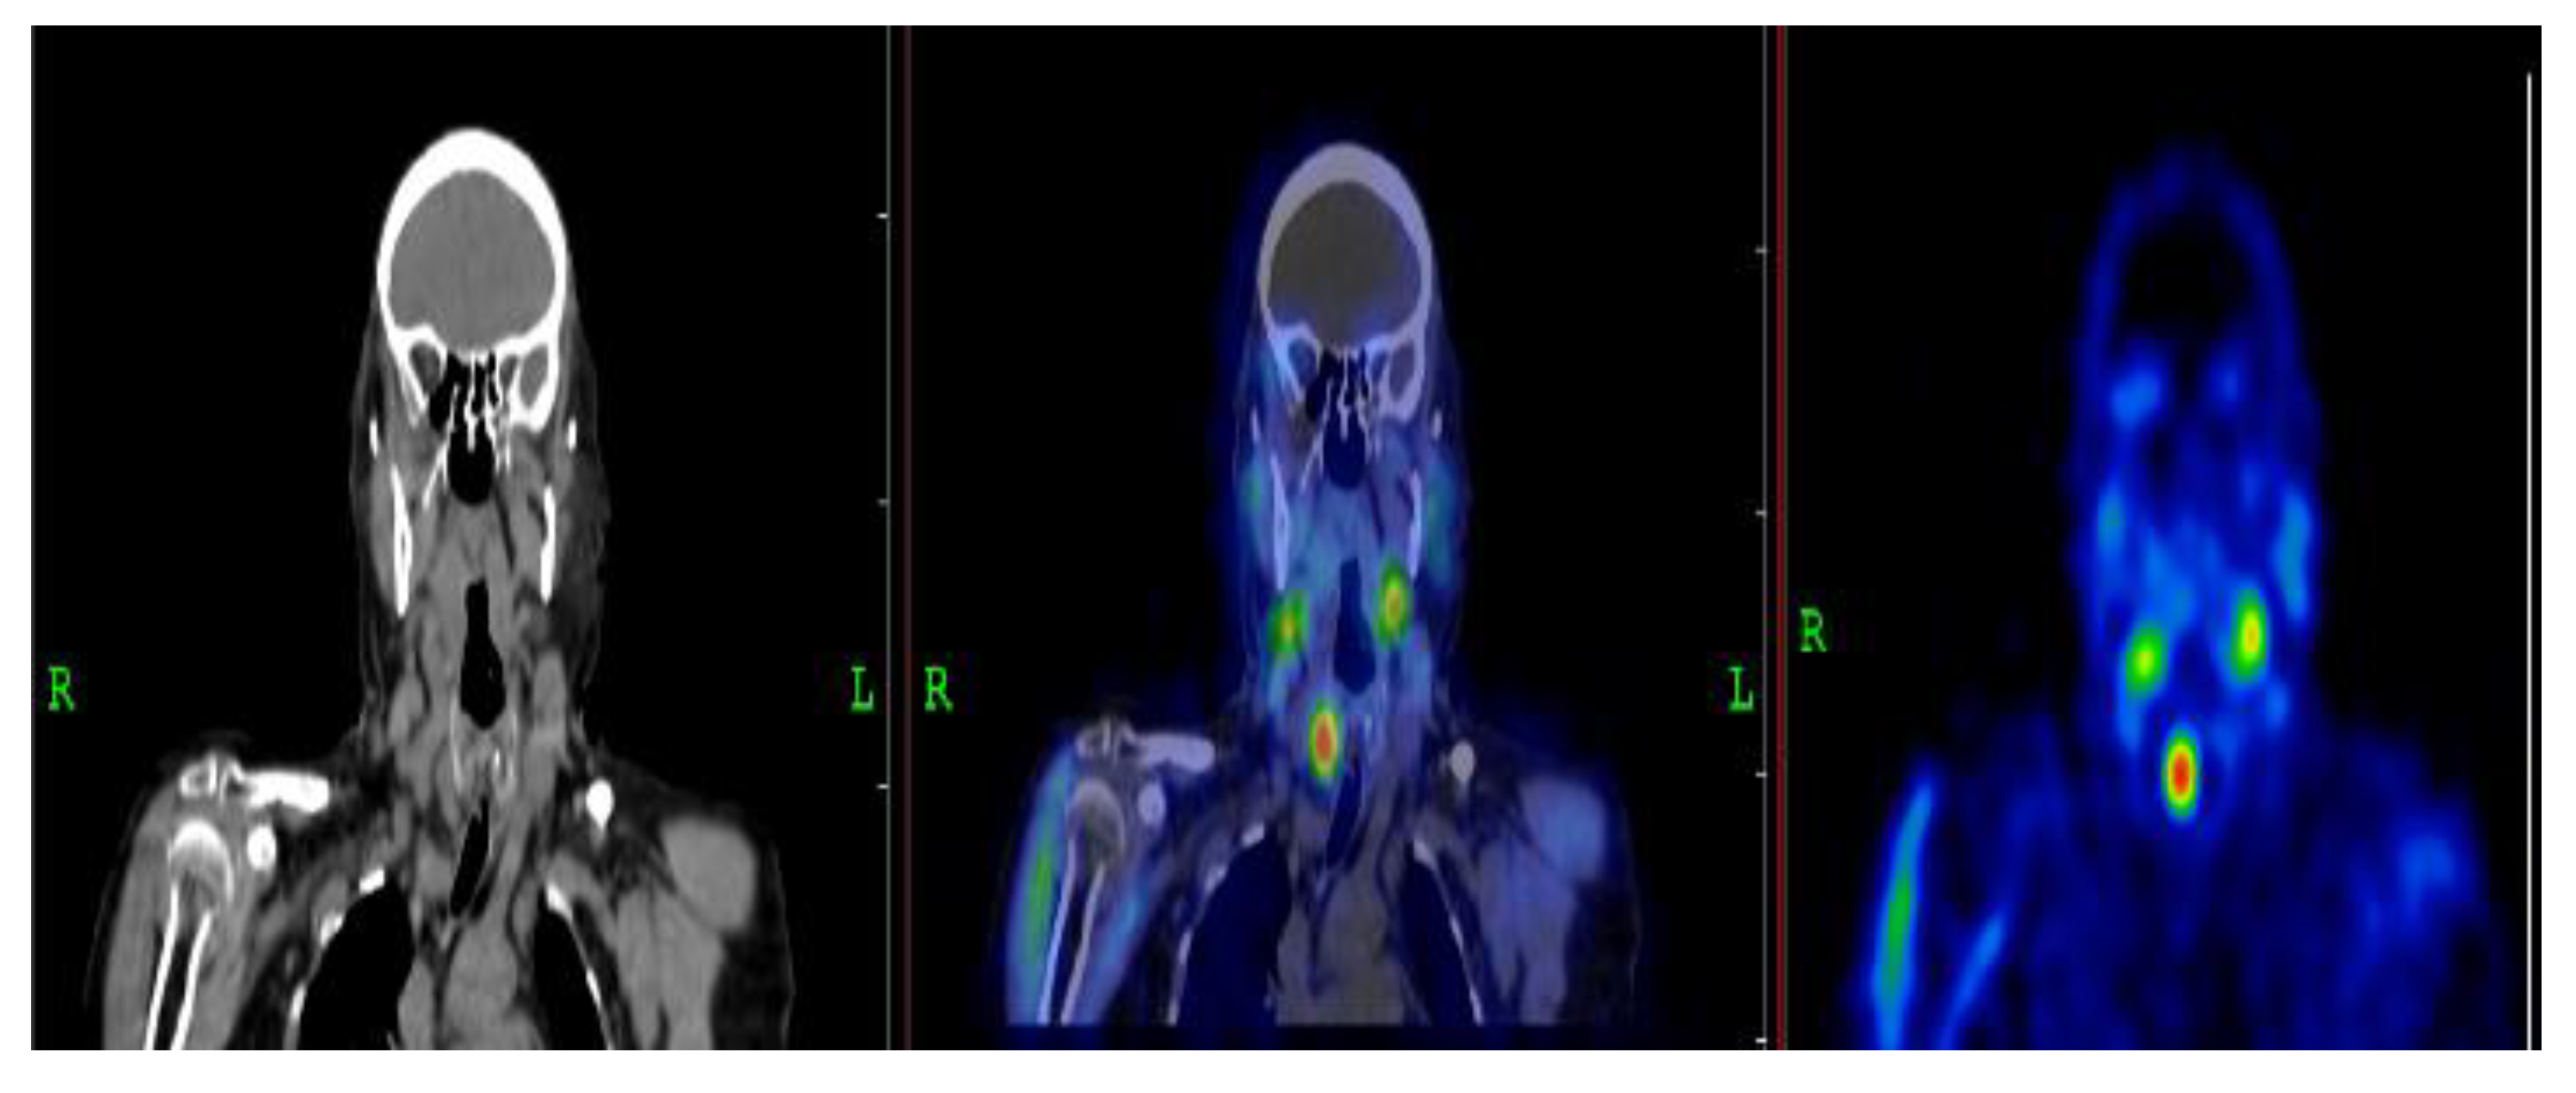

3.2.1. Representative Clinical Case 1